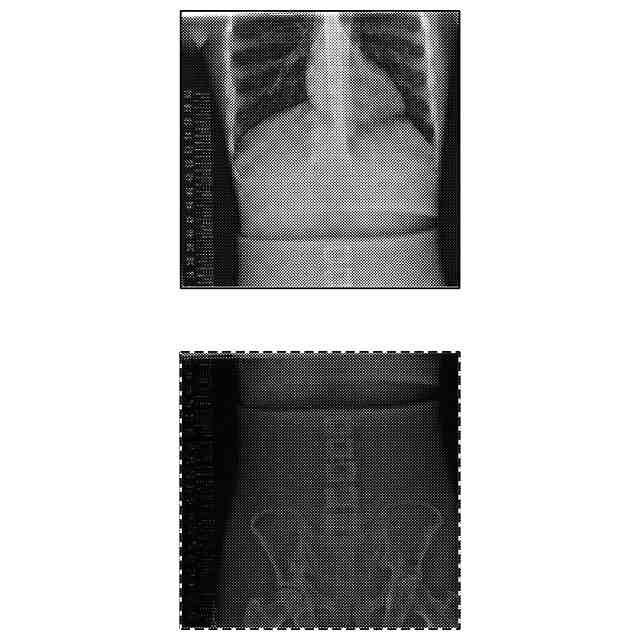

【解決手段】放射線画像処理装置として機能するコンソール30は、被写体に対し、それぞれ異なる撮影条件で撮影した複数の放射線画像を取得する画像取得部として機能する制御部31と、複数の放射線画像のうち少なくとも一の放射線画像の画素値を補正する画素値補正部、複数の放射線画像を合成して一の合成画像を取得する画像合成部として機能する画像処理部36と、を備え、複数の放射線画像の各々の放射線画像は、少なくとも一つ以上の他の放射線画像との画像重複領域を有し、画素値補正部は、少なくとも一の放射線画像の画素値の最大値が、画像の階調の最大値以下となるように画素値を補正する。

従来、放射線源の照射方向を体軸方向に変えることで得た複数の画像を合成させた合成画像を作成する方法(いわゆる首振り長尺)が知られている。

当該方法においては、放射線を複数回被写体に曝射する必要がある。そのため、被写体に健康上の悪影響が生じるおそれがある。そこで、例えば特許文献1及び2には、画像撮影の度に撮影条件を変更することで曝射の影響を抑えて、画像合成時に各画像の画素値を自動で補正する方法が記載されている。

しかしながら、特許文献1及び2には、画素値補正の具体的な方法については記載されていない。そのため、合成画像の画素値が階調の最大値以上となって(いわゆる濃度飽和)黒潰れを起こし、読影が困難になり得る。

前記画素値補正部は、前記少なくとも一の放射線画像の画素値の最大値が、画像の階調の最大値以下となるように画素値を補正する。

前記画素値補正部は、前記複数の放射線画像のうち前記mAs値が最も低い放射線画像の画素値を基準として、他の放射線画像の画素値を補正する。